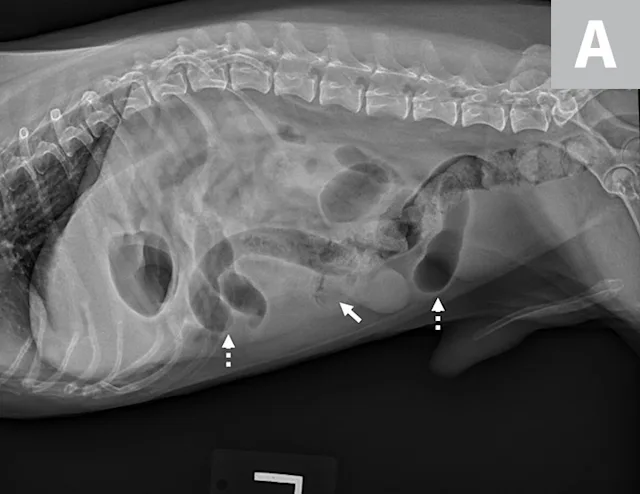

Radiographs can show segmental dilation of the bowel. In dogs, intestinal diameter measurement of >1.6 times the height of the midbody of the L5 vertebra is suggestive of intestinal dilation.1 In cats, intestinal diameter measurement of >12 mm or >2 times the height of the L2 vertebra is suggestive of intestinal dilation.1 Measurements are not definitive but can act as guidelines that can be correlated with clinical signs. As the size of the intestinal dilation increases, so do the concerns for surgical obstruction.

Left lateral image showing segmental dilated gas-filled intestines (dashed arrows) with heterogeneous soft tissue in a small intestinal segment (solid arrow) in a dog. The foreign material was cloth, and the diagnosis was small intestinal mechanical obstruction. Exploratory laparotomy was performed.